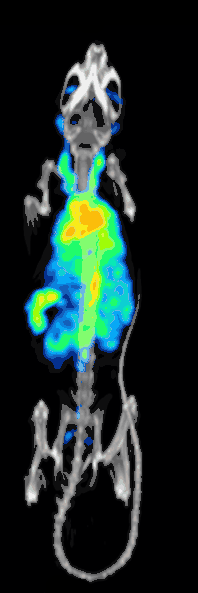

High resolution 99mTc-MDP mouse scan acquired with a stationary SPECT system: animated image of rotating maximum intensity projections.

Fast pharmacokinetics: 15s-frame 99mTc-MDP mouse SPECT scan acquired with a stationary SPECT system